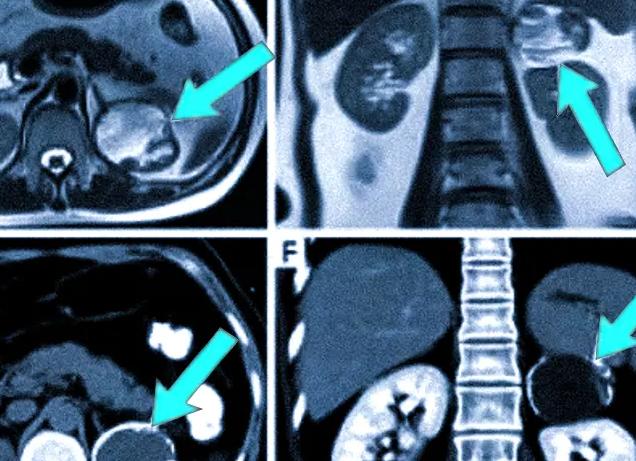

- опухоли и метастатическое поражение почек, надпочечников и околопочечных тканей;

Небольшие в размерах опухоли злокачественного характера обнаруживаются обычно случайно, при плановом обследовании. На полученных изображениях они выглядят как уплотнения неправильного размера, изменяющие природные очертания органа.

Если же новообразование уже определено пальпацией или другими диагностиками, КТ позволяет установить его размеры и точное расположение, наличие метастазов, характерные особенности. Часто раковые опухоли дают о себе знать и другими признаками – болью в спине, наличием крови в урине, общей слабостью.

Так как контрастное вещество лучше всего скапливается в областях локализации опухолей и улучшает визуализацию их структур, исследование позволяет с высокой точностью обнаружить новообразования в почках пациента, определить их четкие границы. По скорости выделения контраста почками специалисты могут судить о состоянии их выделительной функции.

КТ почек позволяет обнаружить самые различные отклонения, которые легко определяются по изменению плотности. Так, при наличии новообразований на снимках будут видны участки, плотность которых отличается от плотности паренхимы, также и форма и границы почки могут меняться при наличии кист, раковых опухолей, некротических очагов и т.д.